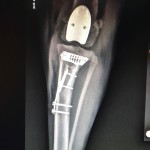

Beremiz Sánchez, encontró que Chavy presentaba luxación patelar grado IV -es decir que su rótula salió del surco de la rodilla-, y como consecuencia de ello sufrió desalineación del músculo cuadricep desarrollando a lo largo del tiempo una enfermedad degenerativa severa en su rodilla.

Además presentaba, ruptura del ligamento cruzado craneal, condición muy común en caso de luxación patelar y que predispuso a una mayor inestabilidad e inflamación articular.

El especialista detalló que el procedimiento a efectuarse era colocar un surco protésico para mejorar su condición biomecánica y contrarestar el dolor.

El procedimiento fue realizar el reemplazo del surco troclear PGR (patellar group replacement). “Se reemplazó el surco degenerado por una prótesis de titanio extra pulido o ultra pulido. Esta prótesis lo que busca es tener una superficie articular sumamente lisa para evitar que haya un roce inadecuado entre la rótula y la superficie articular degenerada”, indicó el especialista en ortopedia.